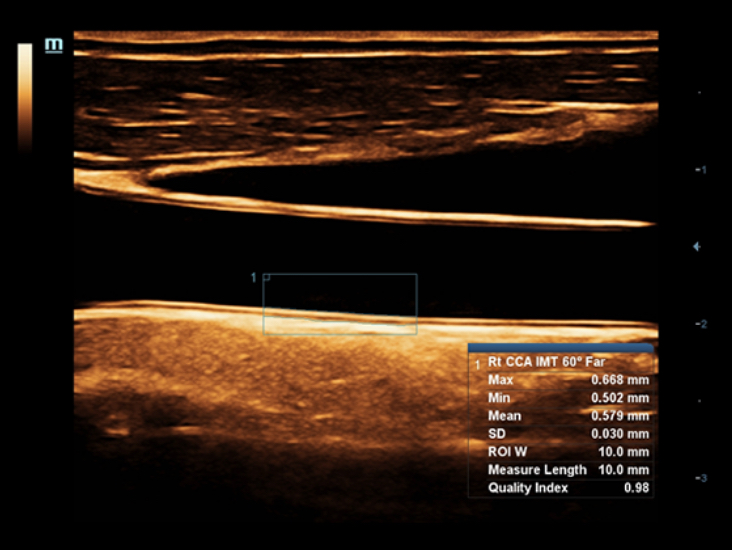

Специализированный уход благодаря ECHO

Многофункциональная система DC-60 Exp с X-Insight представляет собой комплексное решение, которое помогает управлять повседневной клинической практикой с легкостью и уверенностью.

Основываясь на глубоком понимании потребностей клиентов, компания Mindray разработала систему DC-60 Exp с X-Insight, чтобы обеспечить высокую производительность и точность визуализации вкупе с наглядностью, исключительной интеллектуальностью и огромным опытом.

Опыт работы и высокая производительность